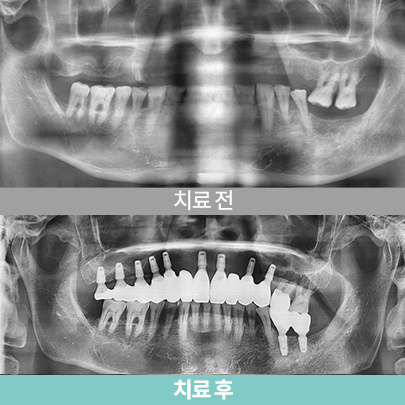

- 송곳니 발거+골이식+임플란트식립, 치료 후 5개월

- 골소실 부위 임플란트

-

- 송곳니 발거+골이식+임플란트식립, 치료 후 5개월

- 골소실 부위 임플란트

-